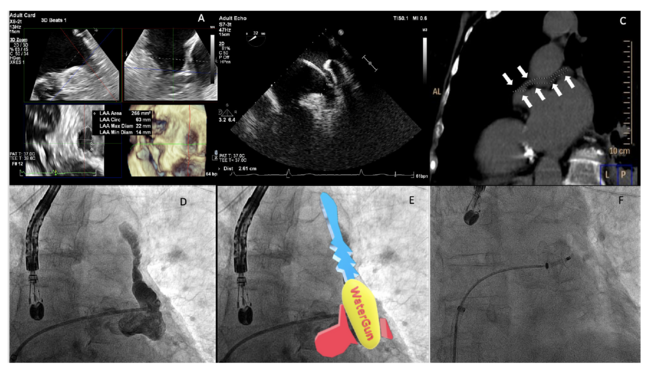

The transesophageal echocardiogram (TEE) performed the previous day evaluated the morphology and dimensions of the LAA and ruled out any thrombus (Figure 1A). During the procedure, a pigtail catheter was inserted into the LAA, observing an unusual image. For this reason, a JR4 catheter was used to perform a selective angiography (Figure 1B; Video Series) and an exploratory crossing attempt was performed with a Radiofocus guidewire (Terumo), confirming a cul-de-sac without an anomalous connection with any drainage in other vessel or cavity. After verifying this finding in a computed tomography performed 4 years earlier (Figure 1C), we concluded that it was a non-previously described morphology of the LAA, which we have termed “water-gun” morphology (Figures 1D, 1E). The LAA closure was performed successfully with a 25-mm Amulet device (Abbott Vascular) (Figure 1F; Video Series). At 3-month follow-up, there were no complications.

The study of the morphology of the LAA is crucial for an adequate implantation of an LAA closure device. Four morphologies have been described based on the shape of the central and secondary lobes. To the best of our knowledge, this is the first description of a fifth type, the “water-gun” morphology, which was shown to be effectively closed with current closure devices.